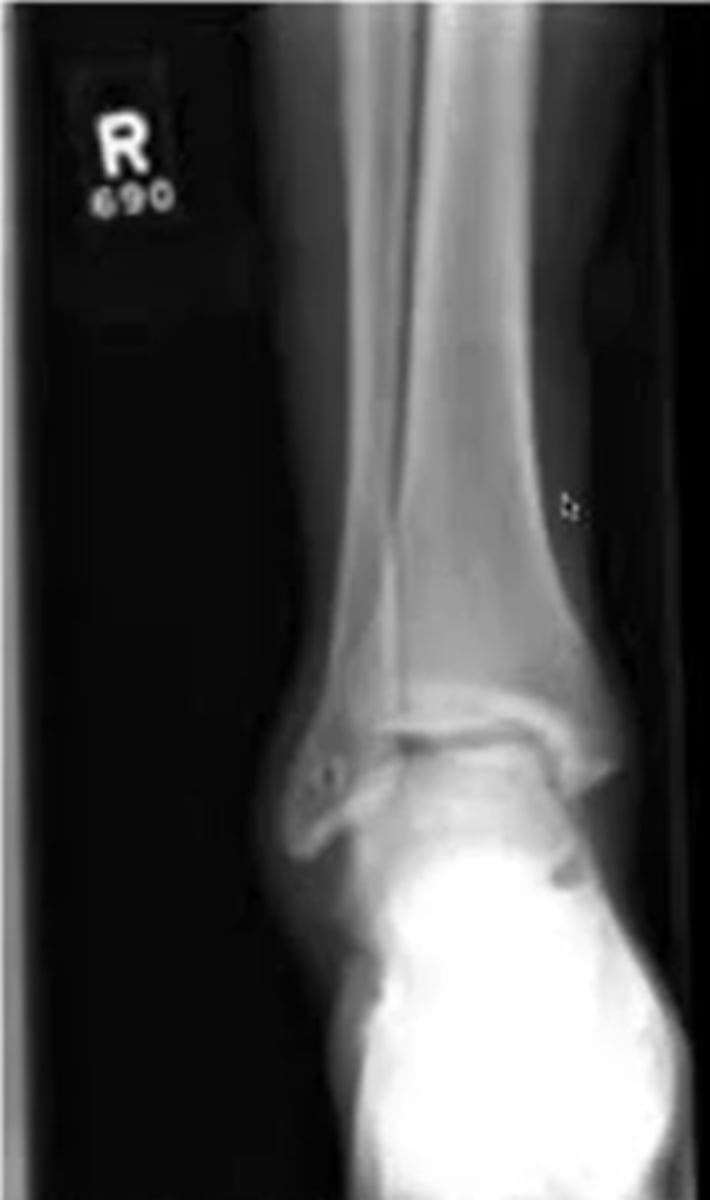

what does a right anterior to posterior view of the ankle look like

this is a right ankle facing you in anatomical position